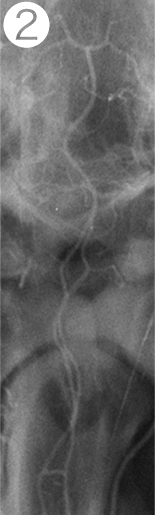

モデル動物の脳血管に原因物質SPCを投与して検証

①SPC投与前の血管

⇒正常な血管の状態

②SPC投与2時間後の血管

⇒SPCを一回投与しただけで2時間もの長い間

広範囲で著明な血管の異常収縮が認められた